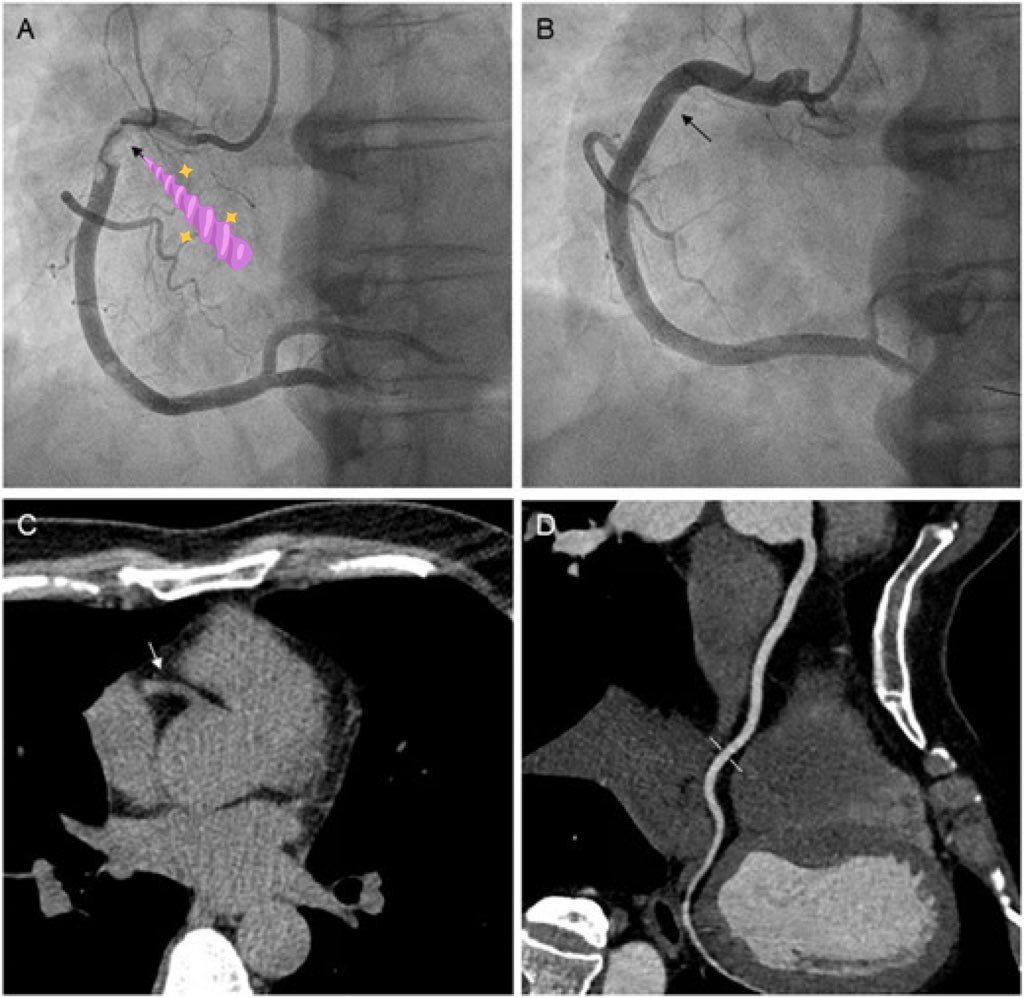

Bisakah serangan jantung tanpa nyeri dada?